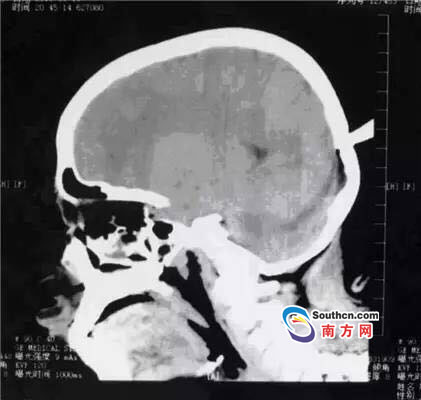

接到小玲受傷的消息,東莞市第三人民醫(yī)院急診科立即啟動了急癥危重患者搶救流程。急癥頭部CT顯示,飛鏢已穿透小玲的顱骨,并突破硬腦膜,情況非常兇險(xiǎn),小玲命懸一線。